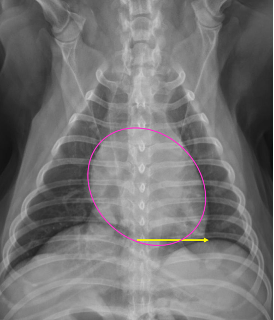

How do we measure heart size on rads

Vertebral heart score

-put the heart width and length along the vertebrae starting at T4 = cumulative sum of vertebra between length and with = vertebral heart score

Normal vertebral heart score in dogs and cats

Dog 8.5-10.6 (9.7)

Cat 7.5 ± 0.3